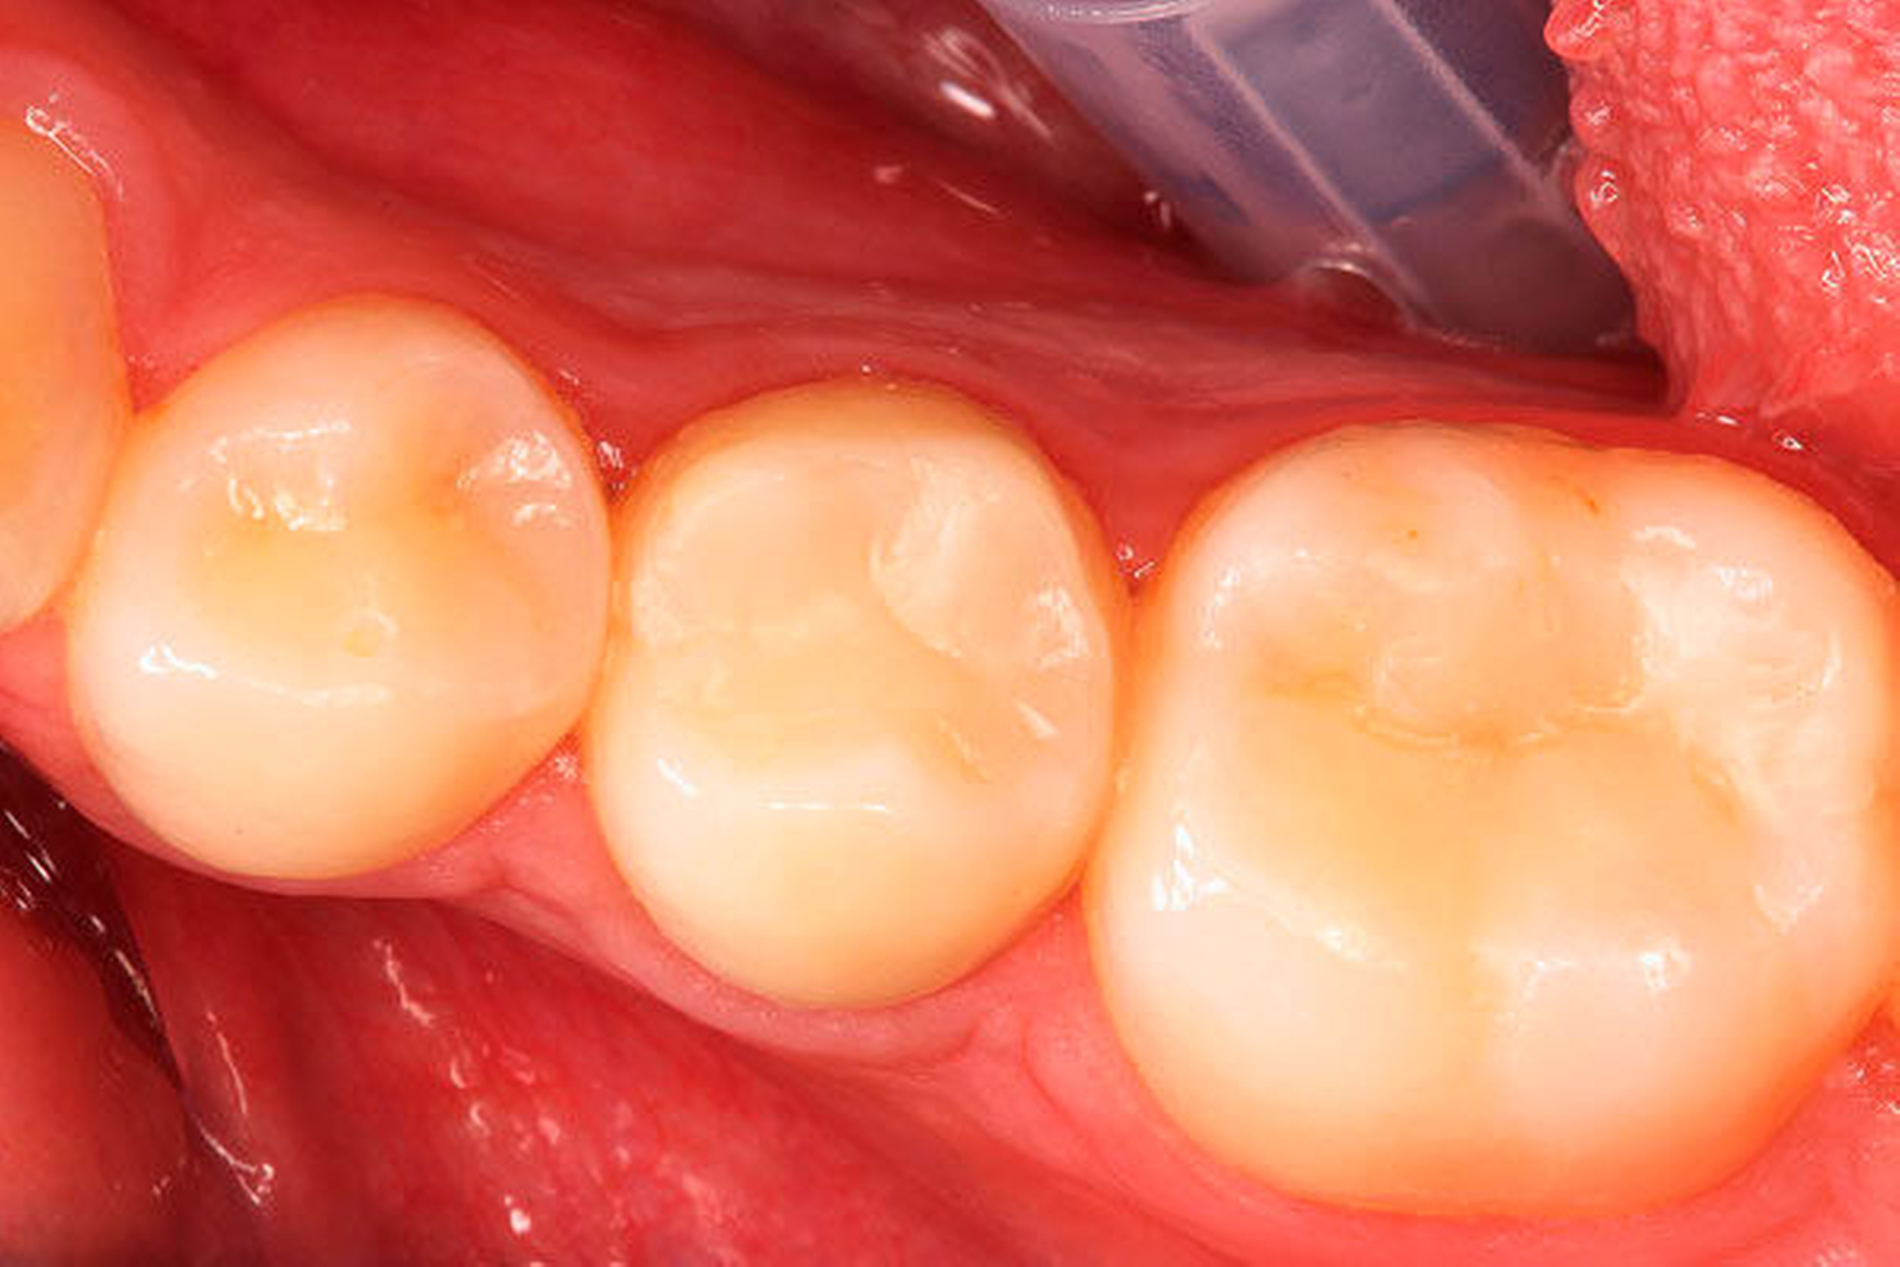

Klinisch stellte sich der Zahn als nicht perkussionsempfindlich dar und reagierte nicht auf den Kältetest. Es lag keine Schwellung vor, jedoch ein Fistelgang lingual des Zahnes 45 (Abbildung 2) sowie eine leichte Druckdolenz im Vestibulum Regio 45. Eine große Kavitation, wie es das Röntgenbild vermuten lässt, war klinisch nicht festzustellen (Abbildung 2). Die Nachbarzähne reagierten adäquat auf den Kältereiz und waren perkussionsunempfindlich. Die Fissurenversiegelung an Zahn 46 wurde als insuffizient bewertet.